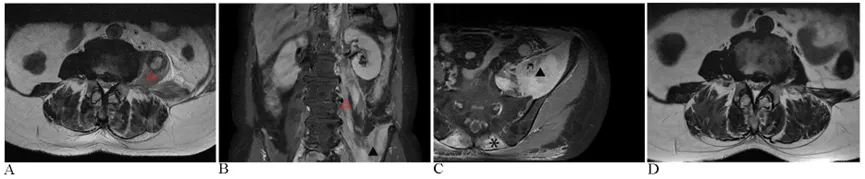

图1 调整治疗前后的图像

(A)初步MRI评估显示T2加权序列上左腰大肌(△)明显肿胀。(B)造影剂增强的冠状MRI显示,钆喷酸二葡甲胺给药后,左髂腰肌(▴)和腰大肌存在异质性高信号强度。(C)增强轴位MRI进一步显示左侧髂腰肌弥漫性肿胀,以及双侧竖脊肌(*),表现出明显的异质信号强度;腰部区域也存在皮下筋膜水肿

。(D)开始连续糖皮质激素治疗后25天,MRI成像显示与图像A相比,肌肉肿胀显著减轻。